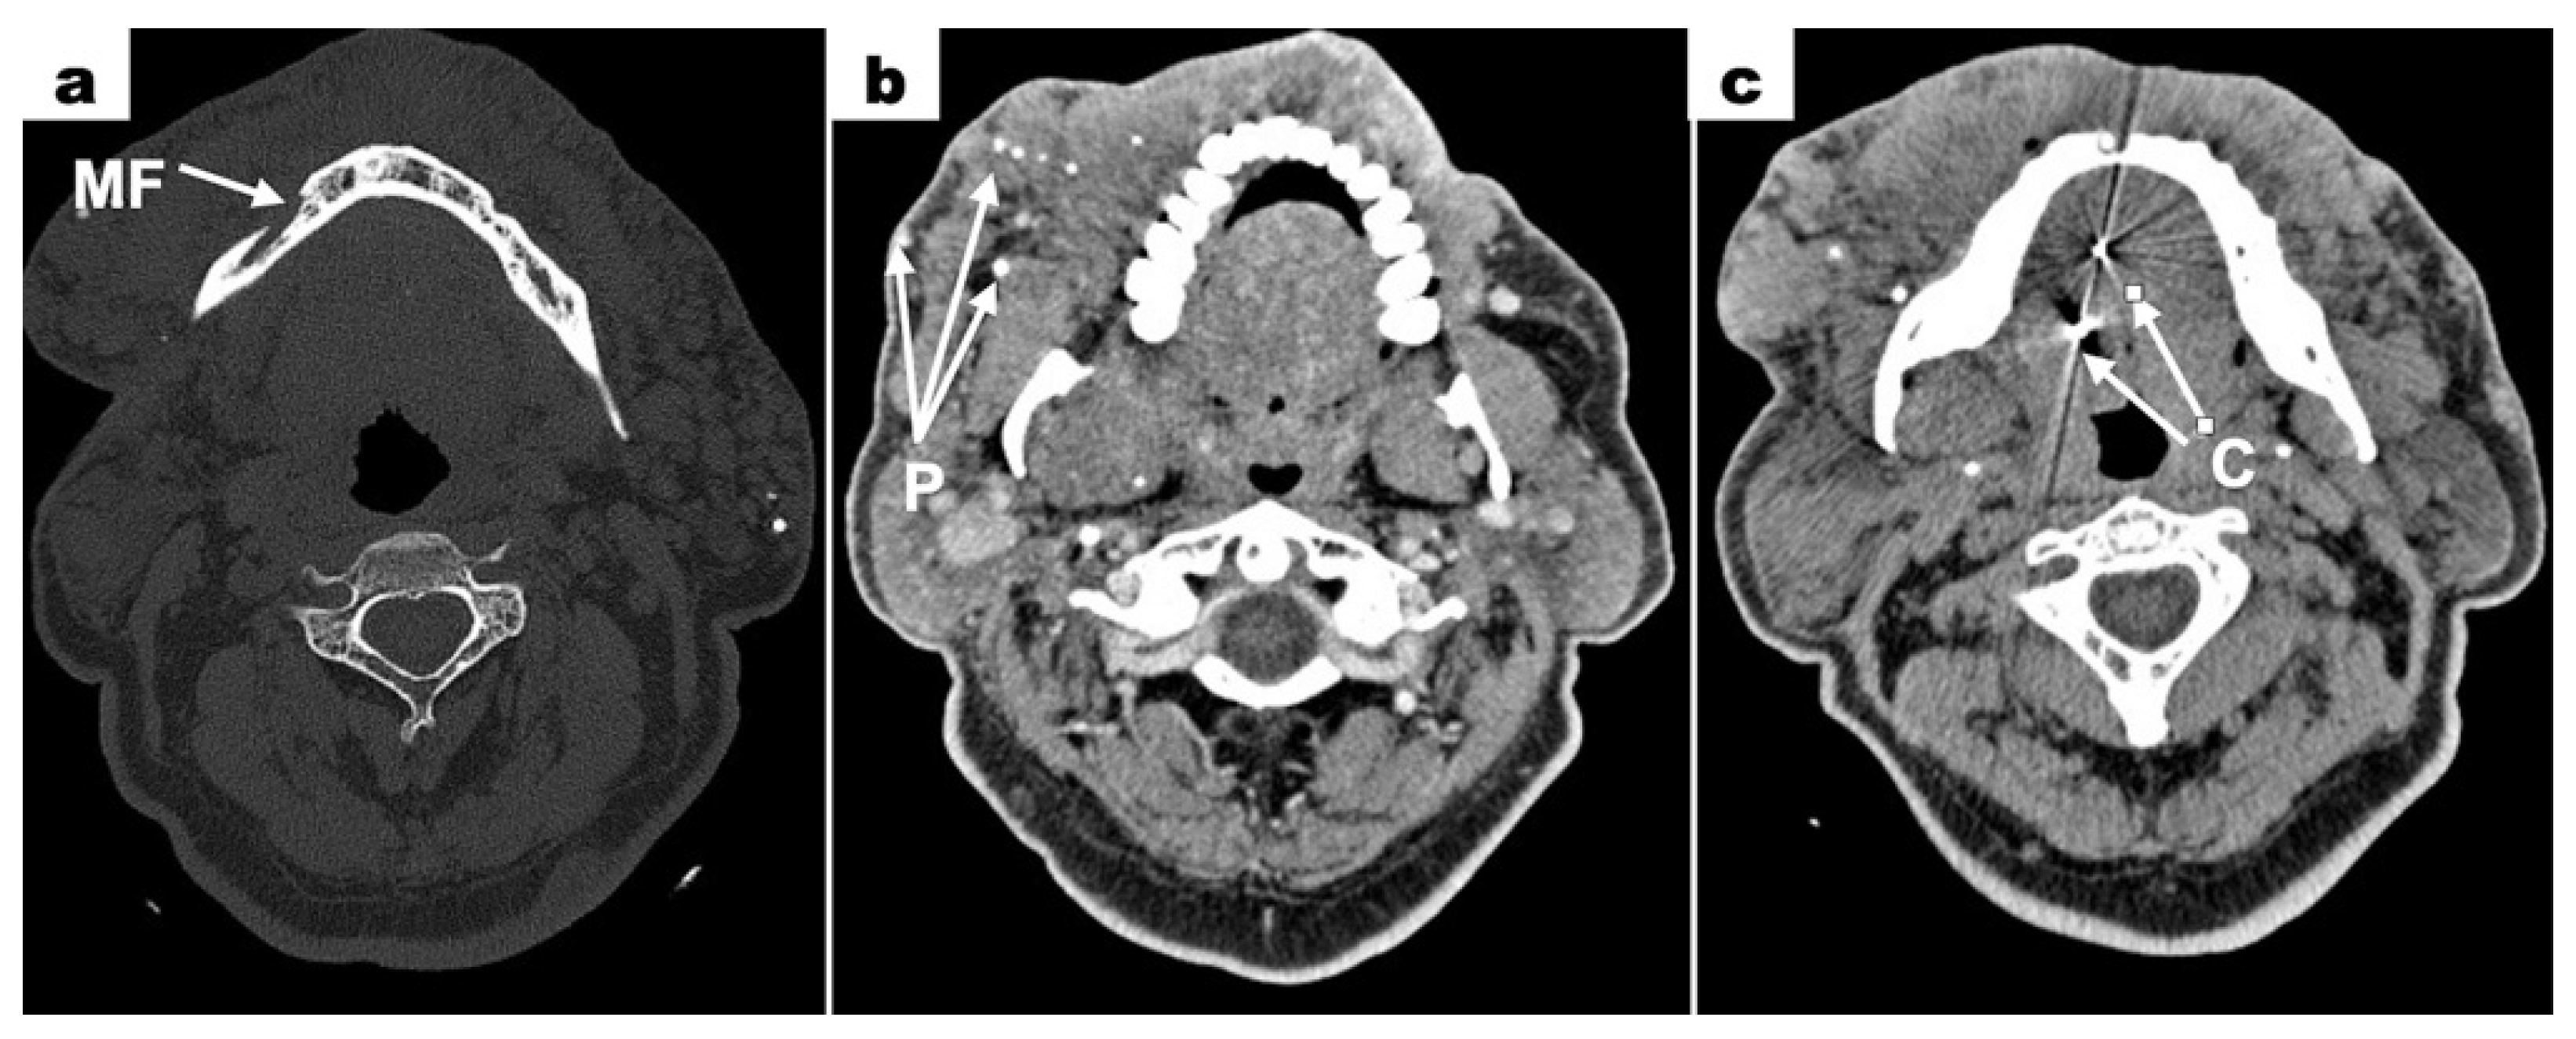

Computed tomography (CT—computed tomography) scans revealed a bone defect measuring 7 × 4.5 mm surrounding the root of tooth 31. Within this area, a tissue mass measuring 12 × 9 mm was observed, partially enhanced after contrast administration. The left mandibular canal was enlarged. Contrast enhancement was noted around the left mental foramen (Figure 5a). The image confirmed the lack of a clear boundary between the mental foramen and the vascular malformation mass. This suggested the infiltration of the vascular malformation into the mental foramen only on the left side. Extensive areas of densification with calcifications were visible in the skin and subcutaneous tissue of the neck, chin, and cheeks (primarily the left cheek) (Figure 5b). Among these, dilated vessels were present, suggesting a large vascular malformation. Metallic foreign bodies were visible in the projection of the tongue, which showed heterogeneous enhancement after contrast administration. Two radiopaque spots were visible in the image—clips used in a treatment to tether the tongue in childhood (Figure 5c). The left submandibular gland was not visualized. A densification in the subcutaneous tissue of the right side of the neck, measuring 9 × 3 mm, was noted. No enlarged lymph nodes in the cervical region were seen.

Figure 5. Contrast-enhanced CT scans; (a) lack of a defined boundary between the mental foramen and the vascular malformation mass (MF = mental foramen); (b) extensive areas of densification with calcifications in the blood vessels of the vascular malformation mass (P = phleboliths); (c) metallic foreign bodies in the projection of the tongue—clips used in a treatment to tether the tongue in childhood (C = clips).